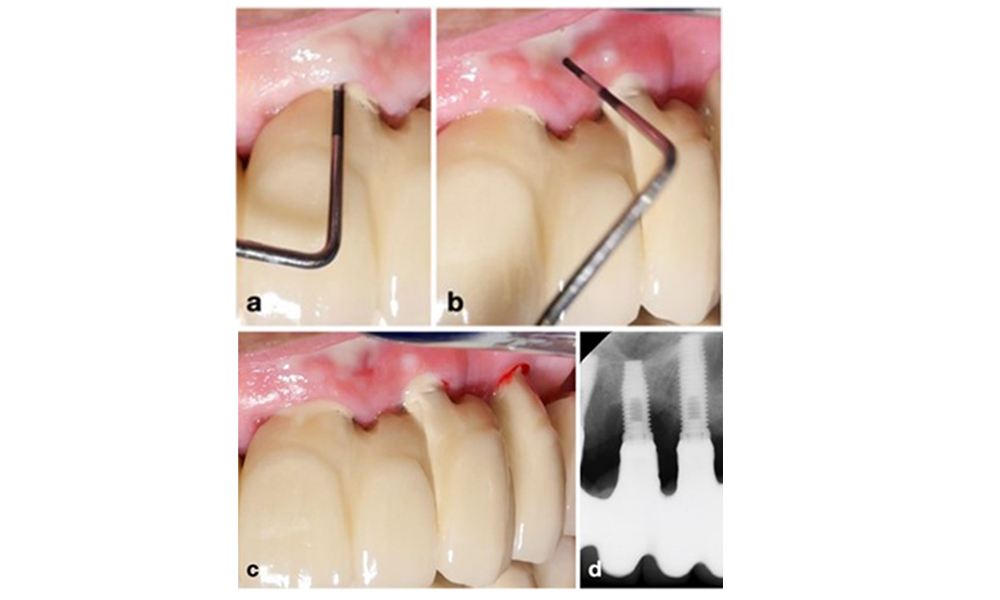

Протетичната реставрация трябва да бъде отстранена както по време на нехирургично, така и по време на хирургично лечение, за да се подобри достъпът до повърхността на импланта. Изборът на хирургична интервенция (напр. резективна, реконструктивна или комбинирана) зависи от няколко фактора: (1) морфология на дефекта (напр. хоризонтална, дехисценция, вътрекостна или комбинирана) (фигура 10), (2) повърхност на импланта ( т.е. обърната или модифицирана/"груба") и (3) наличие или липса на достатъчно кератинизирана и прикрепена лигавица.

Морфологията на дефекта е един от параметрите, определящи вида на хирургичната интервенция. Докато периферните вътрешнокостни дефекти (a) могат да бъдат лекувани добре с реконструктивни процедури, хоризонталните костни дефекти (b) изискват по-резективен подход.

Фигура 10. Морфологията на дефекта е един от параметрите, определящи вида на хирургичната интервенция. Докато периферните вътрешнокостни дефекти (a) могат да бъдат лекувани добре с реконструктивни процедури, хоризонталните костни дефекти (b) изискват по-резективен подход.